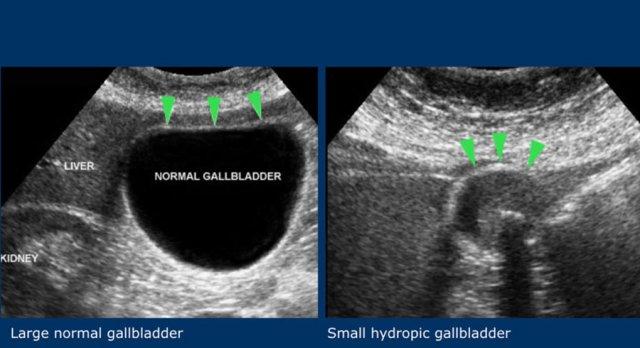

Dấu hiệu thứ ba là đường kính ngang của túi mật lớn.

Đây không phải là dấu hiệu đáng tin cậy, vì đường kính túi mật có biên độ dao động rộng.

Một túi mật 2,5 cm có thể đang phình to và một túi mật có đường kính 5 cm có thể hoàn toàn bình thường (hình).

Do đó, tính không xẹp khi ấn đè và sự duy trì hình dạng tròn trong khi ấn đè vẫn là các dấu hiệu siêu âm đặc trưng của phình to túi mật.